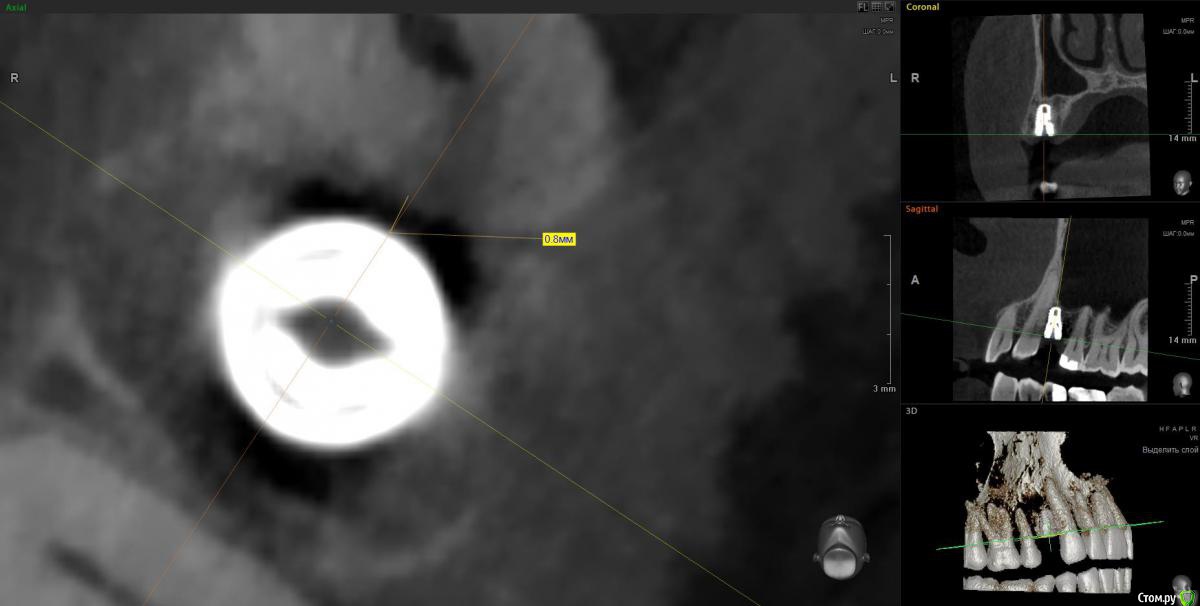

It'sGeorgy Опубликовано 14 апреля, 2020 Поделиться Опубликовано 14 апреля, 2020 Вчера одномоментно. кт только сегодня. Жалоб нет. Хотя там и сст с неба. конечно клык не сверленый, но близость напрягает. Съехал он при установке. Поленился снимок делать после установки, ушил лунку с трансплантатом, во рту норм выглядел. А потом на рг не очень) контроль кт Оставить? убрать недели через 3?Если есть уверенность, что в следующий раз получится поставить лучше и успешно провести ЗСЛ - я бы убрал. Какие показания к удалению? Я бы оставил, не вижу проблемы 0.7 мм рисково между зубов и винтом, на мой взгляд оставлять. Ну и по глубине тоже, ябдокрутил. Ссылка на комментарий

Doctor Vlad Опубликовано 14 апреля, 2020 Поделиться Опубликовано 14 апреля, 2020 Если есть уверенность, что в следующий раз получится поставить лучше и успешно провести ЗСЛ - я бы убрал. 0.7 мм рисково между зубов и винтом, на мой взгляд оставлять. Ну и по глубине тоже, ябдокрутил. было такое в практике, чем опасно? Ссылка на комментарий

Irouil Опубликовано 14 апреля, 2020 Поделиться Опубликовано 14 апреля, 2020 глубины мало?Платформа впритык к зубу, риск формирования кармана очень велик 1 Ссылка на комментарий

Irouil Опубликовано 15 апреля, 2020 Поделиться Опубликовано 15 апреля, 2020 Объясните-в чем опасность? Не понимаю...На уровне шейки, на мой взгляд, будет карман. По вертикали не хватит тканей чтобы обеспечить биологическую ширину Ссылка на комментарий

Doctor Vlad Опубликовано 16 апреля, 2020 Поделиться Опубликовано 16 апреля, 2020 Объясните-в чем опасность? Не понимаю...С зубом проблем не будет, имплант без компрессии там лежит и не травмирует. Но в плане протезирования и долгосрочной перспективы хочется видеть его ровней и на равном удалении от зубов. следующий имплант будет уже. ось его на центр выходит между 13 и 15 но 1 мм от платформы до 13 зуба маловато. Опыта в таких случаях нет. В нижних резцах тоже бывает меньше мм 1 остается и все норм. Хотелось бы поглубже. Сейчас он на мм 2 заглублен от кортикалки и мм 3.5 по десне. но пройдет ремоделировка и будет меньше, а может и нет. Если бы я его протезировал может быть оставил бы посмотреть. Ссылка на комментарий